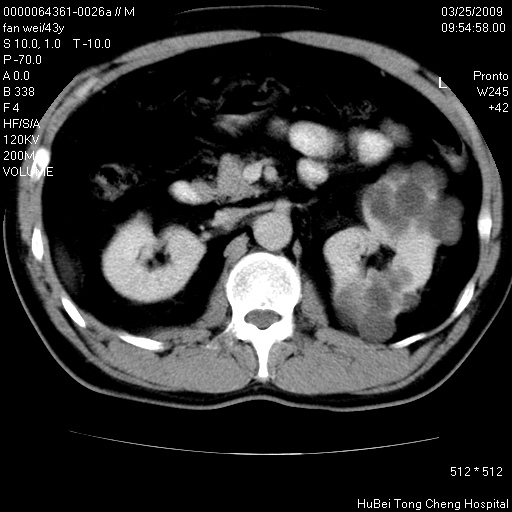

患者 男,43岁。左侧腰部不适两天。平素健康。无家族遗传病史。

临床诊断:左肾多发囊性占位性病变,性质待定(多发肾囊肿?)。

双肾ct轴位平扫+增强扫描(层厚10mm,螺距1.0,重建间隔10mm),图像如下:

多囊肾的影像诊断标准:有阳性家族史,年龄<30岁,单侧或双侧肾脏有两个肾囊肿;30~59岁,两侧肾脏各有两个肾囊肿;60岁以上,每侧肾脏有4个囊肿。敏感性和特异性达86%和80%。

此病例影像诊断符合,要结合家族史,腰痛、血尿、尿路感染史,有无高血压等综合判断,如无相应的临床症状,本身病变也无意义了(个人观点)